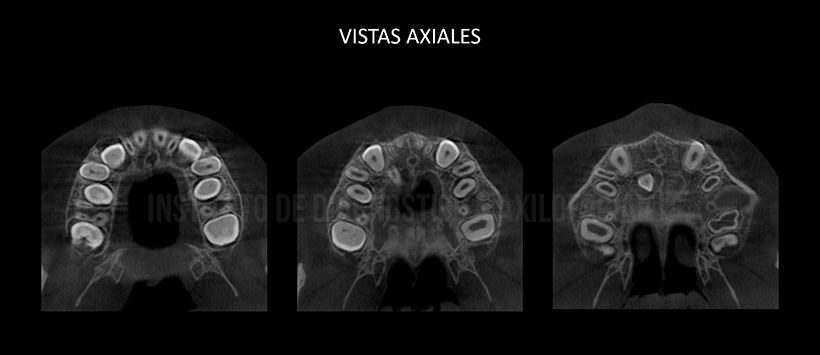

A la evaluación de la tomografía volumétricas de haz cónico se evidencio la presencia de una pieza supernumeraria localizada en el paladar duro y en posición vertical, próxima a las piezas 13 y 12. Así mismo el segmento coronario se encuentra orientado hacia el piso de fosa nasal de lado derecho, presentando un aumento de saco pericorornario. (Figura 2 y Figura 3)